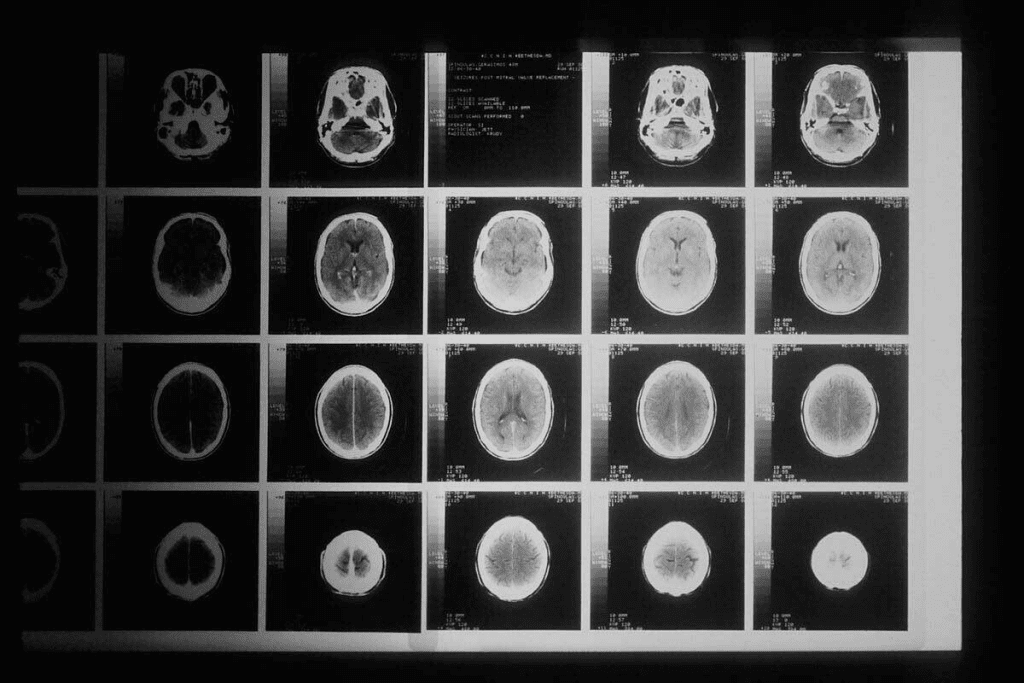

Overview of X-ray, CT, MRI, and Ultrasound Technologies

There are many medical imaging technologies. Each has its own strengths and uses. X-ray technology uses electromagnetic waves to see inside the body. CT scan technology makes detailed images by combining X-rays.

MRI technology uses magnets and radio waves for soft tissue images. Ultrasound technology uses sound waves to see inside. Knowing how these work helps choose the right imaging for a patient.

Basic Technology: 2D vs 3D Imaging Capabilities

X-rays and CT scans differ mainly in their imaging abilities. X-rays give two-dimensional images, mainly for seeing bones, lungs, and some foreign objects. CT scans, on the other hand, create detailed three-dimensional images with X-ray beams and computer processing.

CT scans’ 3D imaging lets doctors see complex body parts better. They can show detailed images of organs, blood vessels, and soft tissues. This makes CT scans great for diagnosing many health issues.